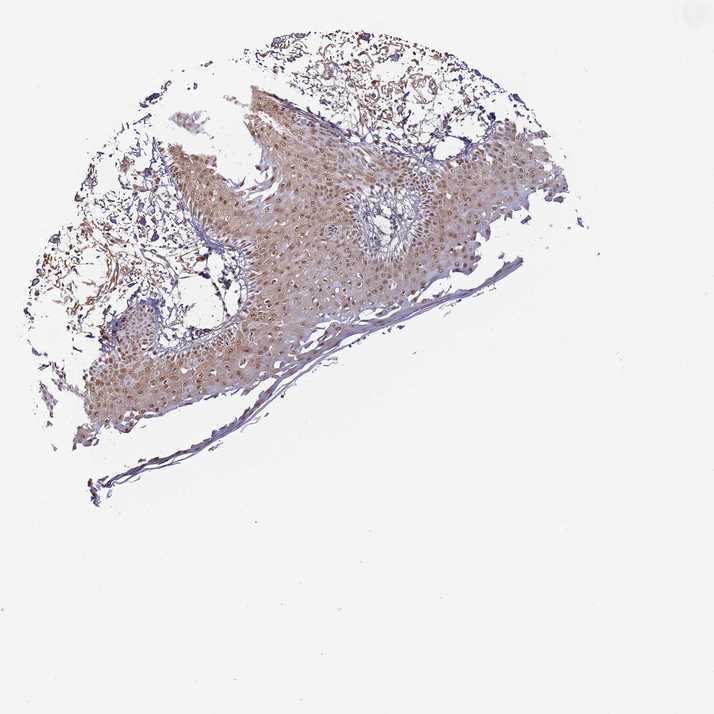

SKIN 2 - Antibody stainingi

Antibody staining in the annotated cell types in the current human tissue is reported as not detected, low, medium, or high, based on conventional immunohistochemistry profiling in selected tissues. This score is based on the combination of the staining intensity and fraction of stained cells.

Each image is clickable and will lead to virtual microscopy that enables deeper exploration of all samples and also displays staining intensity scores, fraction scores and subcellular localization as well as patient and tissue information for each sample.

Antibody HPA043258Antibody HPA043621

Epidermal cells MediumHigh